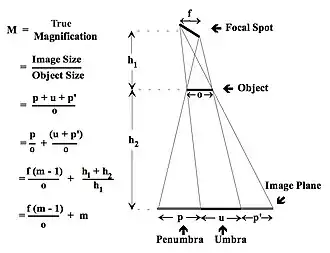

Image Distortion

- The imaging of a flat, opaque object of dimension, o, is considered in Figure 3.12. It can be appreciated that the finite-sized focal spot will now generate penumbra on each side of the umbra, u, of the object. It can also be seen that the penumbra will be of different sizes, p and p’, depending on the angle of the focal spot. Note that the size of the image of the object will be magnified by the geometric magnification as well as a factor depending on the ratio of the focal spot to object sizes. Also note that, at an extreme, as the object’s dimension becomes smaller than the focal spot, the magnification increases rapidly and the penumbral blur can be substantially larger than the umbra itself. In essence, the ability to resolve fine detail will be compromised by the focal spot size.

- On the basis of this discussion, it can be concluded that finer resolution radiographs can be obtained with a smaller focal spot, a large source-to-image distance (SID) and a minimal distance between the body part and the image receptor.

- It should also be appreciated that the beam emerging from a focal spot is shaped by rectangular collimators so that a divergent, rectangular radiation field strikes the patient. We can therefore infer that objects in the peripheral regions of the field will experience a greater magnification and resultant distortions in shape relative to those in the beam’s centre. We can also infer that these effects should increase as we move from the centre of the field to the periphery of the radiation field.

- The unequal magnification effects are illustrated in Figure 3.13. The divergent nature of the X-ray beam can be seen to cause shadows of peripheral disk-shaped objects to become broadened and distorted. The situation in wrist radiography is illustrated in Figure 3.14. Here, the ‘Central Ray’ of the X-ray beam was centered near the trapezium bone and the image represents differences between true anatomical locations and those imaged. It is seen that the best match occurs, as expected, in the region of the Central Ray and that the mismatch increases as we move towards the more peripheral regions of the body part.